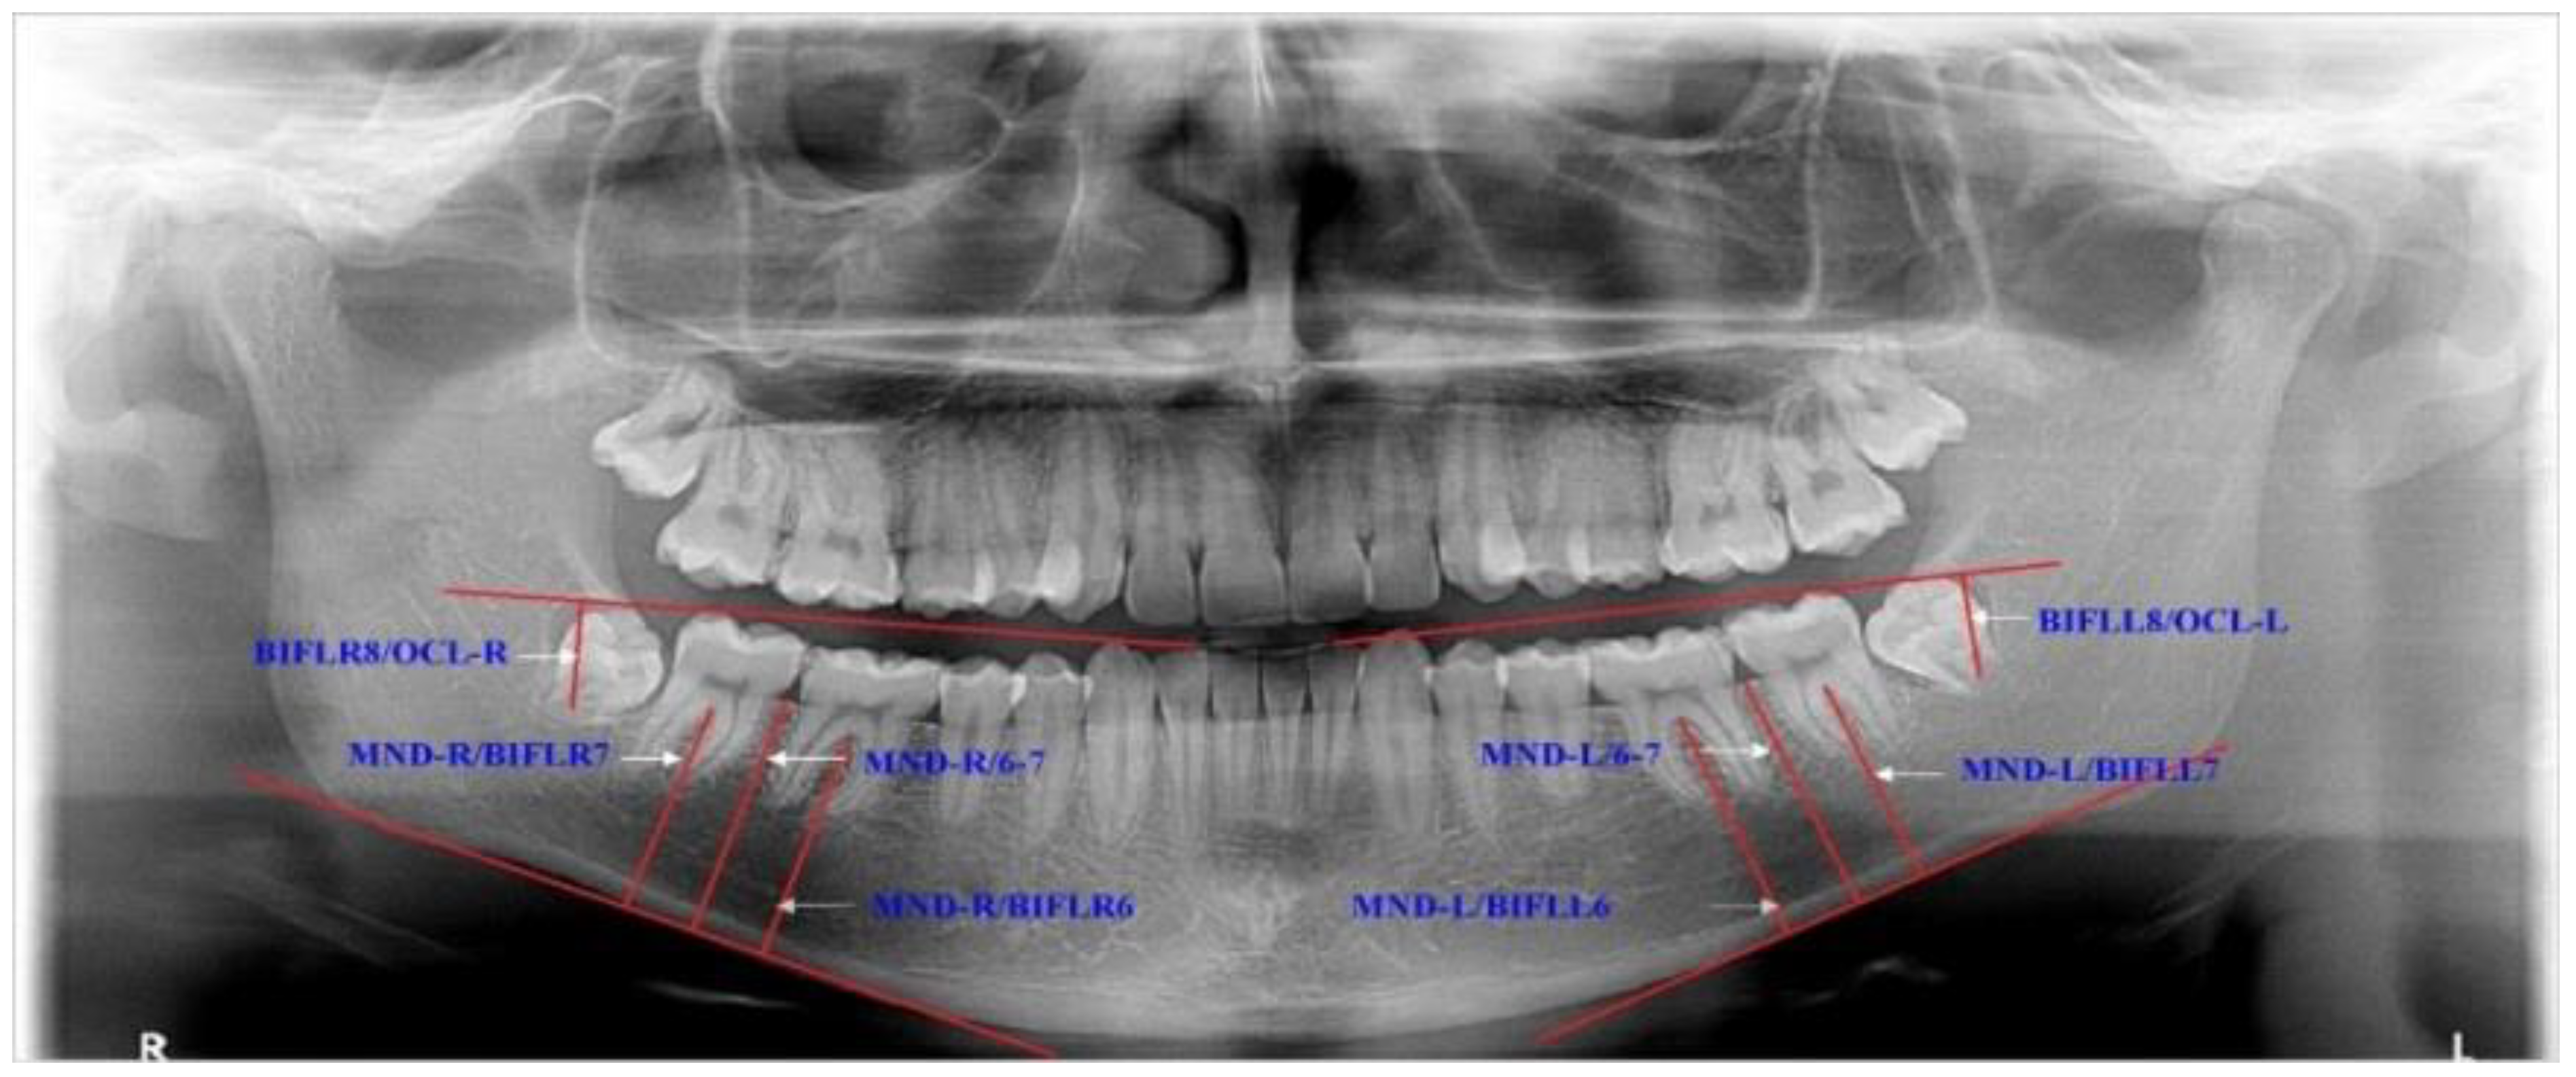

In addition, the eruption levels of lower molars were investigated according to the mandibular and occlusal planes (Figure 2).

Figure 2.

Description of the variables for estimating eruption levels of the lower third molars. MND-R/BIFLR6—the distance from the MND-R plane to the bifurcation of the right lower first molar, and the same with MND-L/BIFLL6; MND-R/BIFLR7—the distance from the MND-R plane to the bifurcation of the right lower second molar, and the same with MND-L/BIFLL7; MND-R/6-7—the distance from the MND-R plane to the edge of the alveolus ridge between the lower right second and first molars, and the same with MND-L/6-7; BIFLR8/OCL-R—the distance from the OCL-R plane to the bifurcation of the right lower third molar, and the same with BIFLL8/OCL-L.